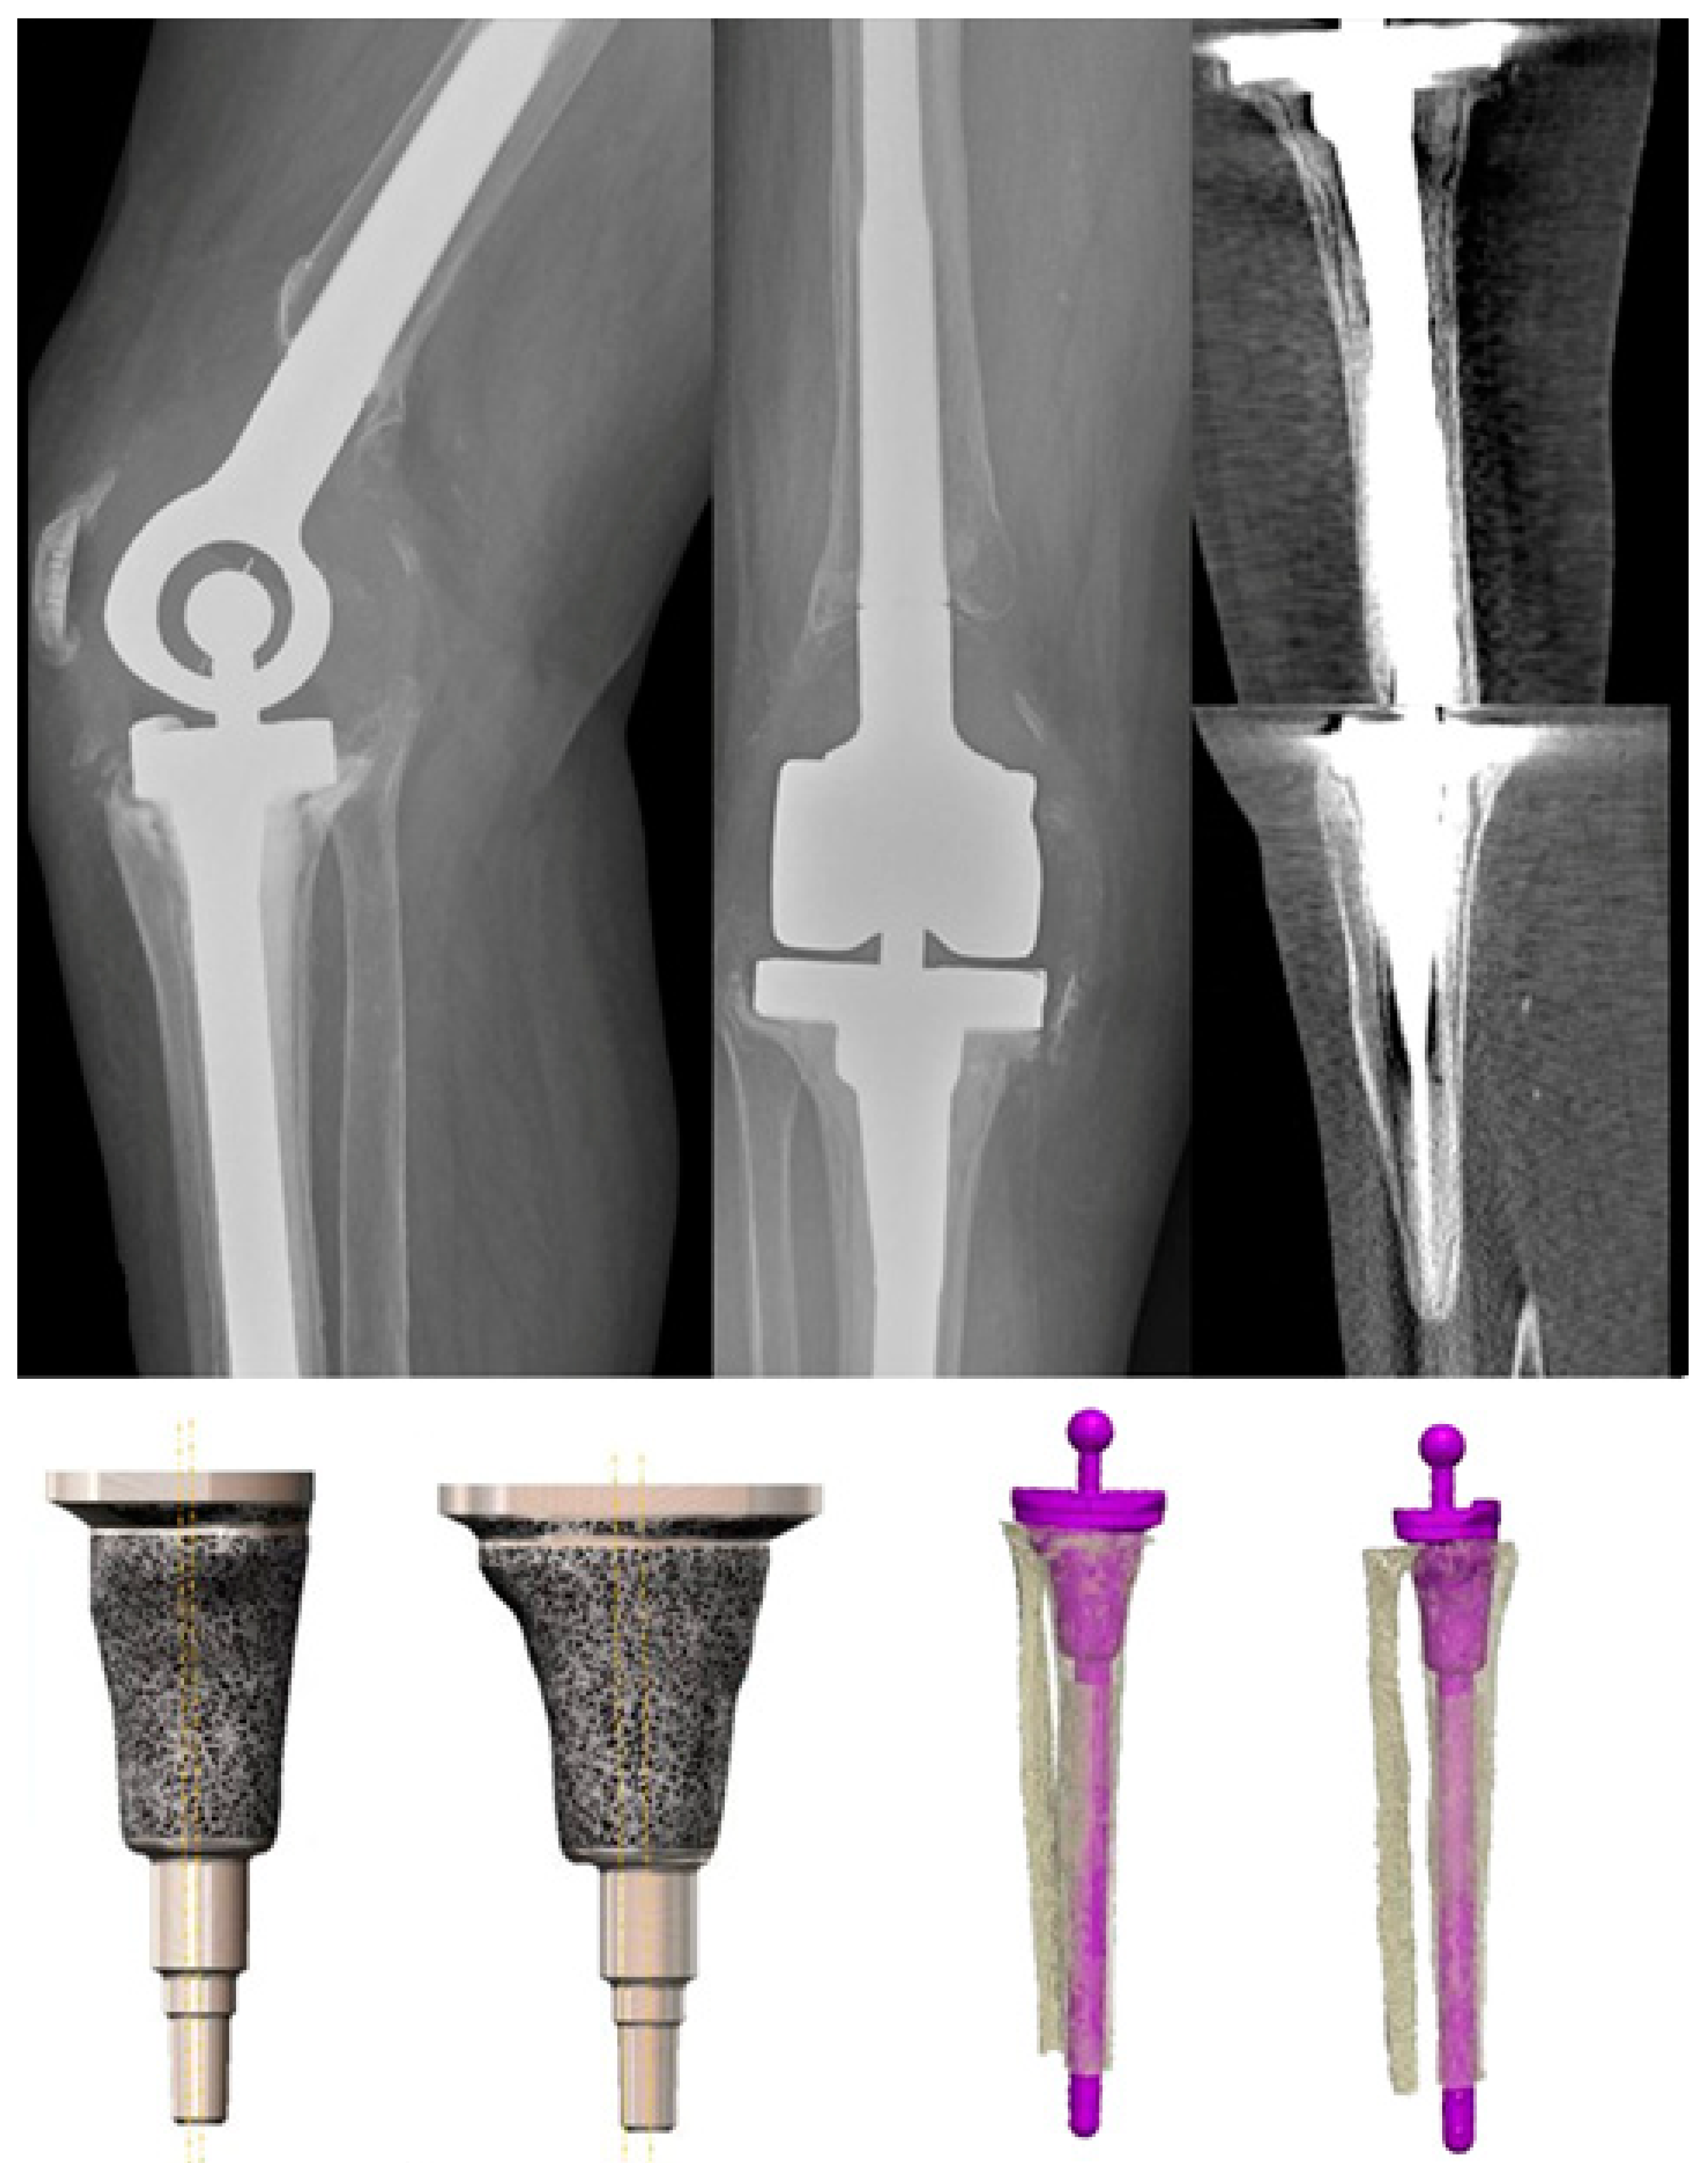

CustomMade Metaphyseal Sleeves in “Beyond” AORI III Defects for Metaphyseal Screw Synthes 6 synthes lcp locking compression plate ordering information basic lcp plates lcp metaphyseal plates 3.5 steel. Use the lcp metaphyseal plate according to the lcp principles (see lcp instructions for use, art. Original instruments and implants of the association for the study of internal fixation — ao asif synthes screw reference chart reference chart screws, drill bits, taps locking screws,. Metaphyseal Screw Synthes.

Metaphyseal Sleeves in Revision Total Knee Arthroplasty Provide Metaphyseal Screw Synthes Use the lcp metaphyseal plate according to the lcp principles (see lcp instructions for use, art. Lcp metaphyseal plate for distal medial tibia. Original instruments and implants of the association for the study of internal fixation — ao asif synthes screw reference chart reference chart screws, drill bits, taps locking screws, guide. 6 synthes lcp locking compression plate ordering information. Metaphyseal Screw Synthes.

JPM Free FullText CustomMade Metaphyseal Sleeves in “Beyond” AORI Metaphyseal Screw Synthes Lcp metaphyseal plate for distal medial tibia. Use the lcp metaphyseal plate according to the lcp principles (see lcp instructions for use, art. Original instruments and implants of the association for the study of internal fixation — ao asif synthes screw reference chart reference chart screws, drill bits, taps locking screws, guide. The 2.7 mm/3.5 mm va lcp™ ankle trauma. Metaphyseal Screw Synthes.

Survivorship of Metaphyseal Cones and Sleeves in Revision Total Knee Metaphyseal Screw Synthes 6 synthes lcp locking compression plate ordering information basic lcp plates lcp metaphyseal plates 3.5 steel. Lcp metaphyseal plate for distal medial tibia. The 2.7 mm/3.5 mm va lcp™ ankle trauma system is a comprehensive plating system that merges variable angle locking screw technology with conventional. Original instruments and implants of the association for the study of internal fixation —. Metaphyseal Screw Synthes.